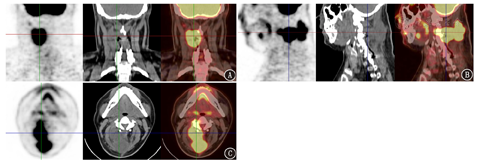

患者男,33岁,2019年1月因车祸导致颈椎过伸伤,于当地医院行颈椎后路减压内固定术;2020年5月30日于外院行自体干细胞颈部脊髓周围注射治疗,6月10日外院颈部MRI示术区软组织未见明显异常占位性病变。患者自诉2020年6月17日出院前发现颈部包块,轻压痛,1个月后发现颈部包块逐渐增大并疼痛加重,触诊示颈部包块边界不清,活动度差,8月20日外院颈椎MRI检查示:颈3~5椎体水平右侧竖脊肌内见等/长T1、长T2信号影,其内信号不均,弥散加权成像序列呈高信号,表观弥散系数图呈低信号,增强扫描病灶呈明显不均匀强化。9月2日入解放军第九六零医院骨病科进一步治疗。18F-FDG PET/CT显像见右侧竖脊肌区FDG代谢增高占位性病变(图1),余部位未见明显异常。结合病史考虑为异常增殖性肿瘤性病变,后行颈部肿瘤扩大切除术。术后病理示肿物内查见鳞状上皮、腺上皮、横纹肌、软骨岛、神经胶质组织及原始神经管等结构,为三胚层肿瘤,诊断为畸胎瘤。该例为干细胞移植治疗后术区局部发生的恶性畸胎瘤,结合治疗过程及病情进展迅速等特点,临床考虑为局部移植干细胞来源可能性比较大,患者术后未行其他治疗。

患者出院后1个月外院颈部MRI检查示颈部软组织见多发团块样、结节状不均匀等T1、长T2信号影,弥散加权成像序列呈高信号,表观弥散系数图呈低信号,另于C3椎体内见斑片状长T1、长T2信号影,T2压脂序列呈高信号。结合既往病史,考虑为干细胞移植来源恶性畸胎瘤复发,再次入院治疗。临床考虑肿瘤无法完整切除,目前行放疗。本例PET/CT显像示明显高摄取18F-FDG的囊实性病变,根据干细胞移植治疗患者的病史及病变部位,PET/CT影像表现可对脊髓损伤干细胞移植治疗后恶性畸胎瘤作出提示性诊断。